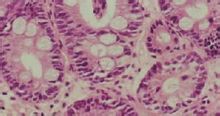

腸上皮化生腸上皮化生是指胃黏膜上皮細胞被腸型上皮細胞所代替,即胃黏膜中出現類似小腸或大腸黏膜的上皮細胞,其是胃黏膜常見病變,見於多種慢性胃病。腸上皮化生細胞來自胃固有腺體頸部未分化細胞,這部分細胞是增殖中心,具有向胃及腸上皮細胞分化的潛能。正常時,它不斷分化成胃型上皮細胞,以補充衰老脫落的表面上皮;病理情況下,它可分化為腸型上皮細胞,形成腸化生。近來有人進一步研究腸化灶的組織學始發部位主要在胃小溝,微小的腸化灶以胃小溝為中心,可以不同程度地向周圍胃小區發展為小灶及大片狀腸化灶。通過病理學的研究,目前對腸上皮化生作了一系列的分類,按化生上皮功能來分腸上皮化生,可分為完全性或不完全性腸上皮化生。前者與小腸黏膜吸收細胞相似,有刷狀緣,不分泌粘液,具有潘氏細胞、杯狀細胞和吸收細胞,含蔗糖酶、海藻糖酶及亮氨酸基肽酶和鹼性磷酸酶;而不完全性腸上皮化生刷狀緣不明顯,微絨毛髮育不全,胞漿內有粘液分泌顆粒,含蔗糖酶,但氨基肽酶和鹼性磷酸酶活性低,無海藻糖酶。

腸上皮化生通過粘液組化染色把腸上皮化生分為小腸型化生(即完全性腸上皮化生)和結腸型化生(即不完全性腸上皮化生)。結腸型化生,其上皮分化差,在良性胃病中檢出率很低(11.3%),但在腸型胃癌旁黏膜中檢出率很高(88.2%),說明結腸型化生與胃癌的發生有密切關係。一般結腸型化生發生的年齡較小腸型化生為晚,而且均位於較重的小腸化生灶中。兩型化生可混合存在,因此結腸型化生可能是在小腸型化生逐漸加重的基礎上發生的。

腸上皮化生:出現腸上皮的杯狀細胞、吸收細胞、潘氏細胞和PAS陽性的具有刷狀緣的細胞。